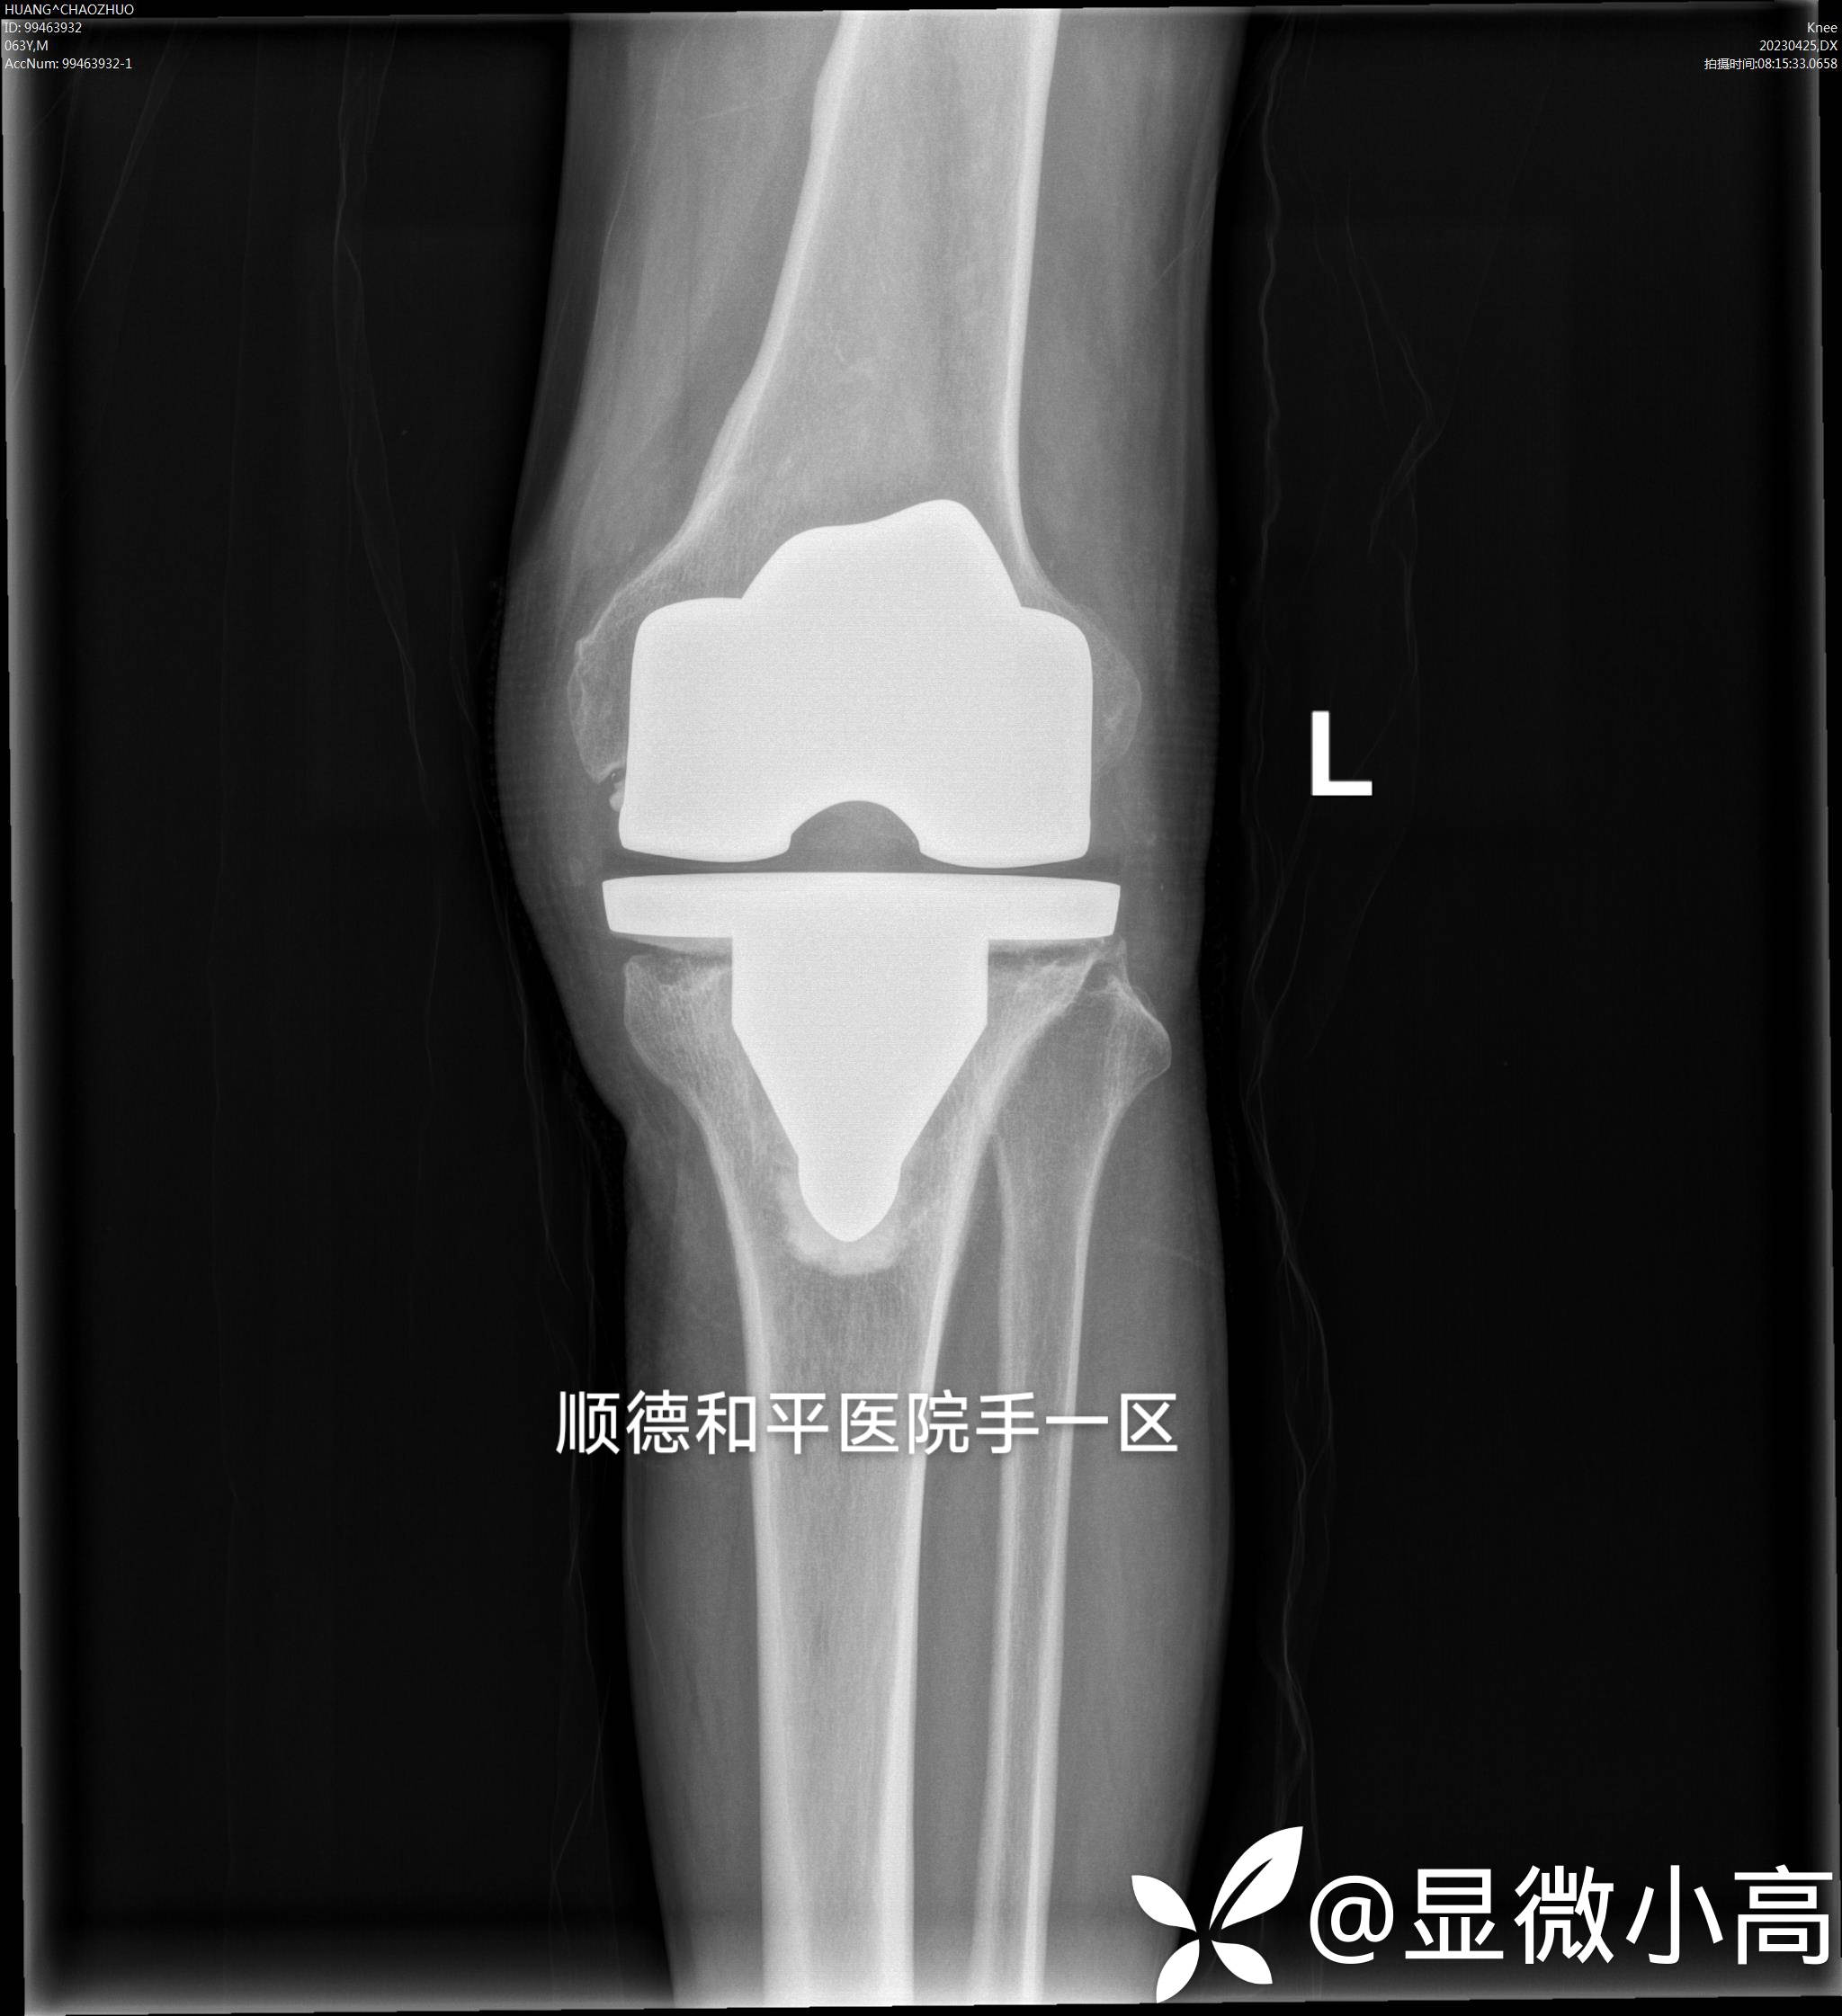

患者 ,男,Y63,诉3年前因左膝骨关节炎行左膝关节置换术,术后20+天即出现膝关节周围红肿胀痛,外院给予切开排脓处理后红肿胀痛得以明显缓解,但是遗留左膝前切排脓切口无法愈合、膝关节红肿流脓迁延不愈持续存在,在外院诊断左膝关节置换术后假体周围感染,此后一直采用抗生素静滴治疗并无好转。伴左下肢夜间静息痛,既往有高血压病史5年,间断口服用药,平时血压缺乏监测,无相关不适,为求进一步治疗来院就诊。

Ⅰ期行:左膝前原切口切开直达髌骨前深筋膜,彻底清创,抗生素骨水泥填塞控感染。